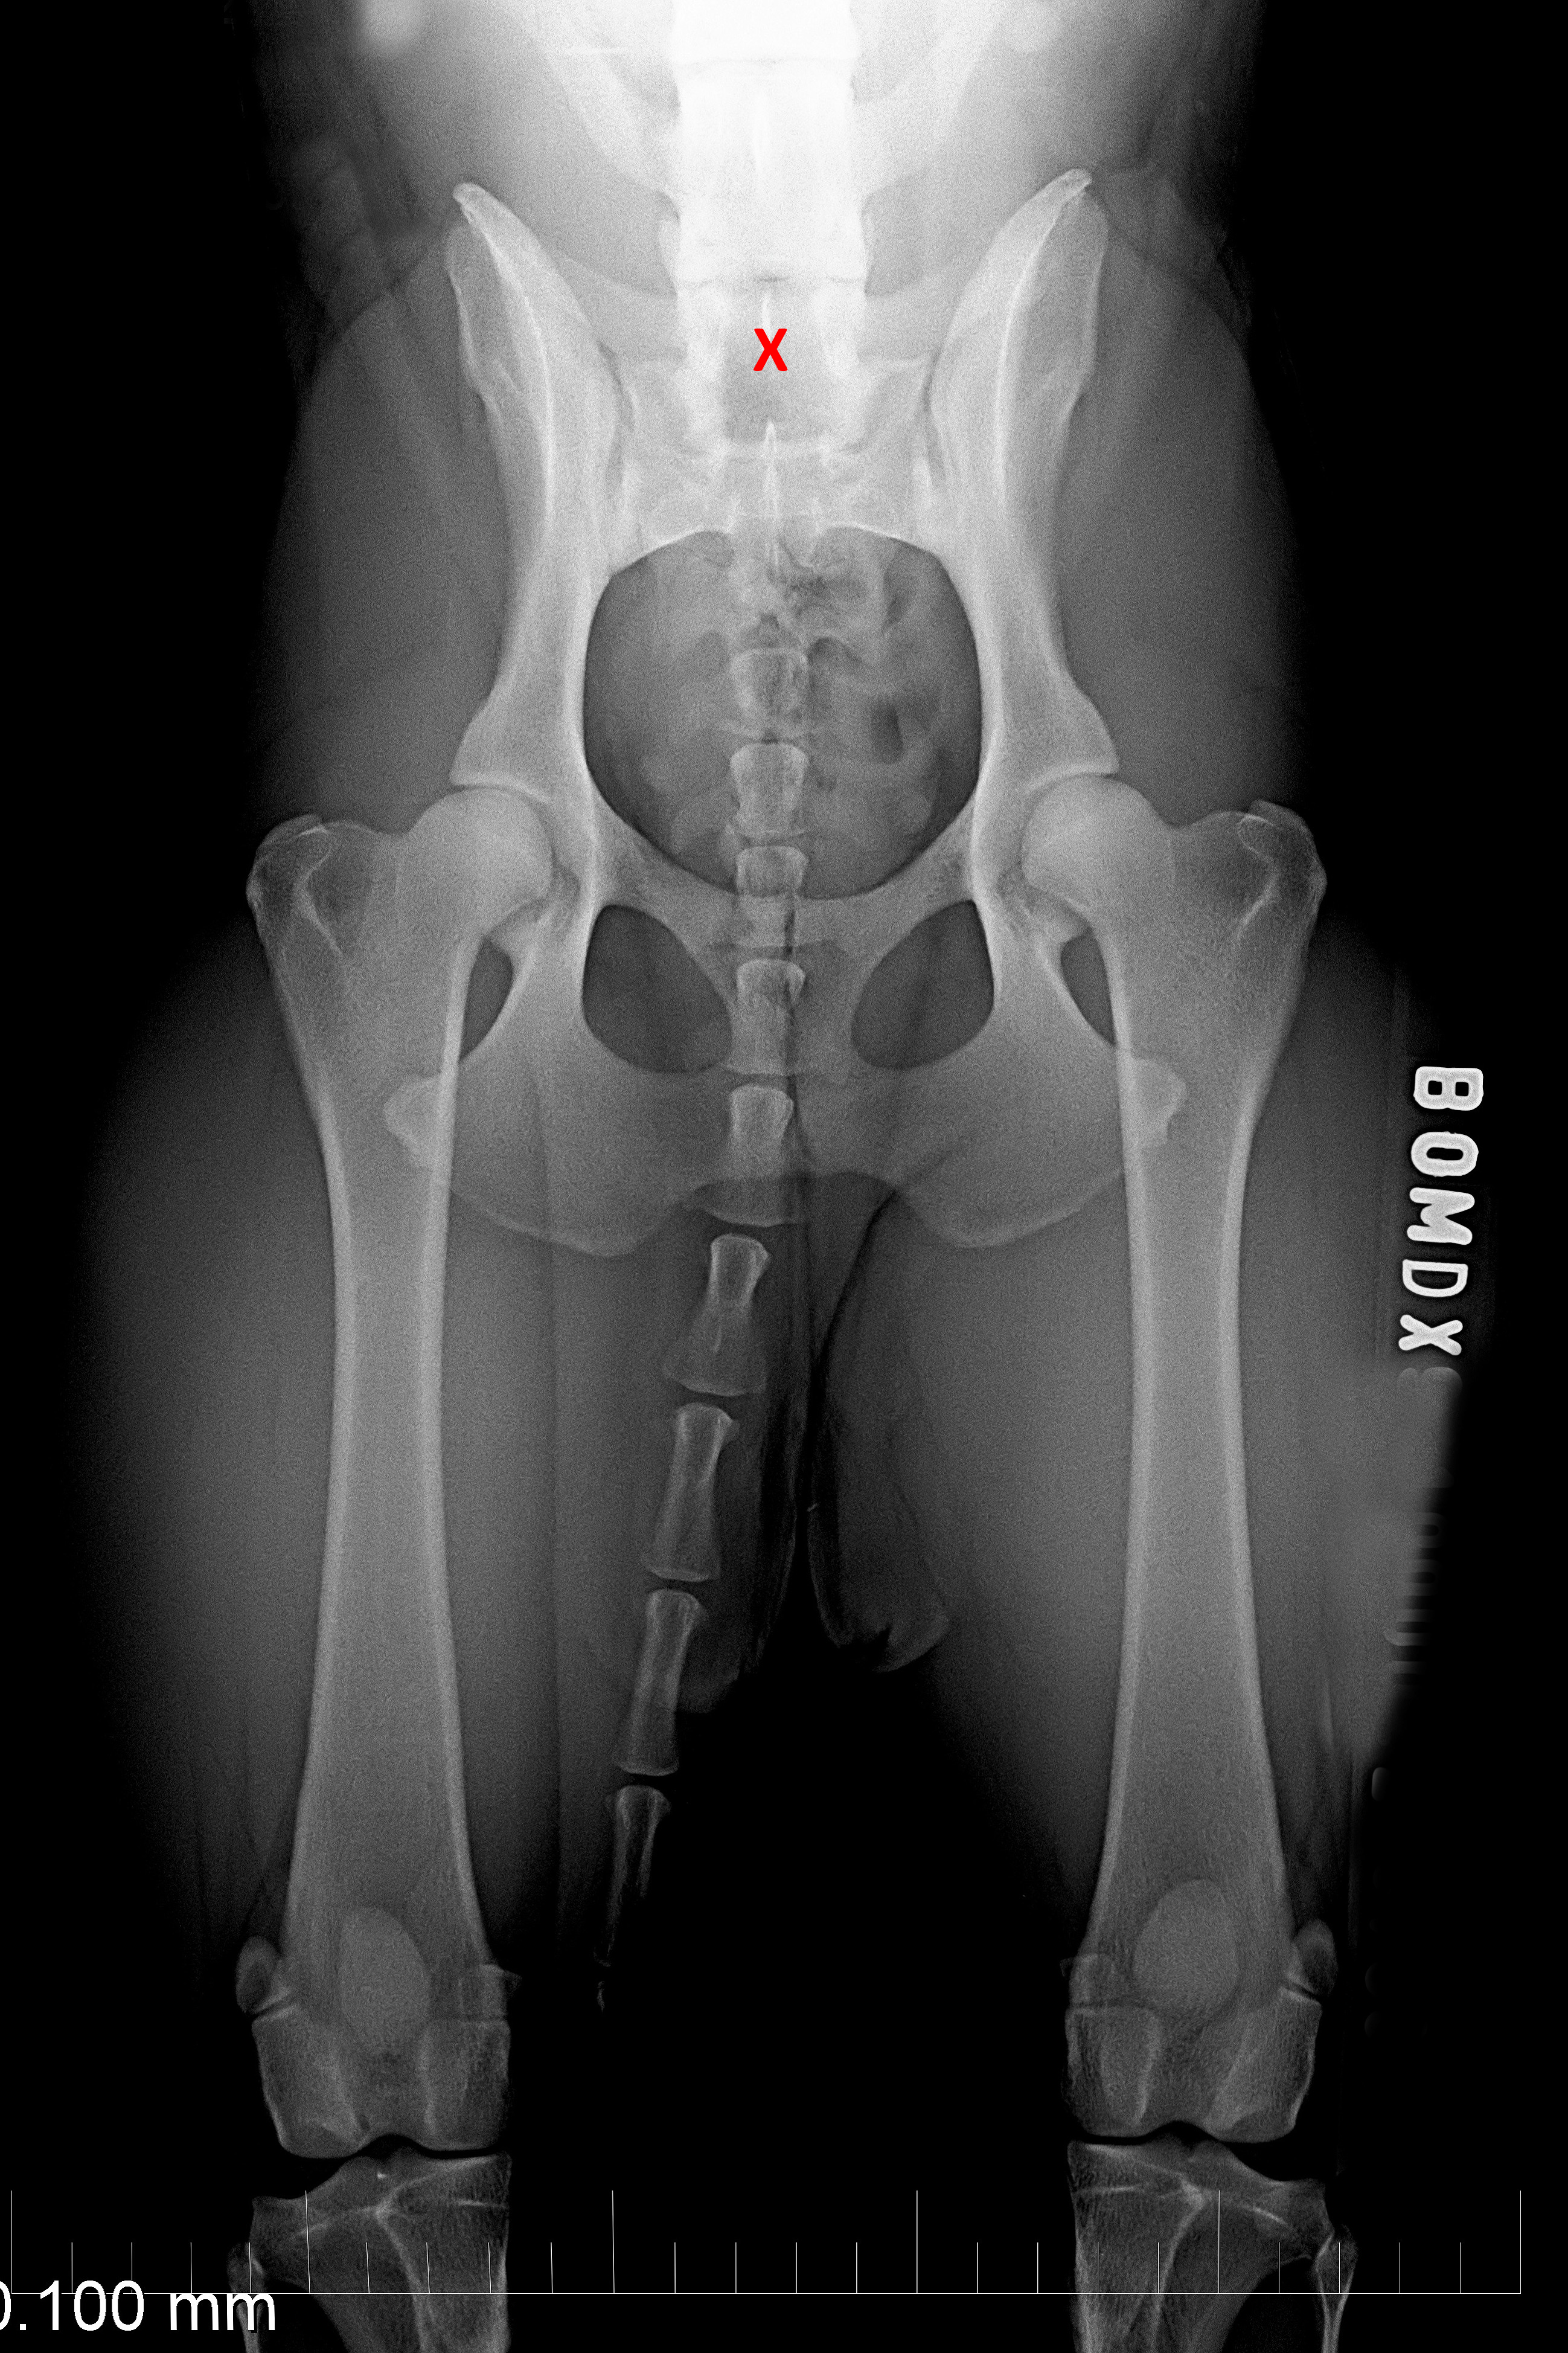

MVDr. Meloun: Lumbosakrální přechodový obratel